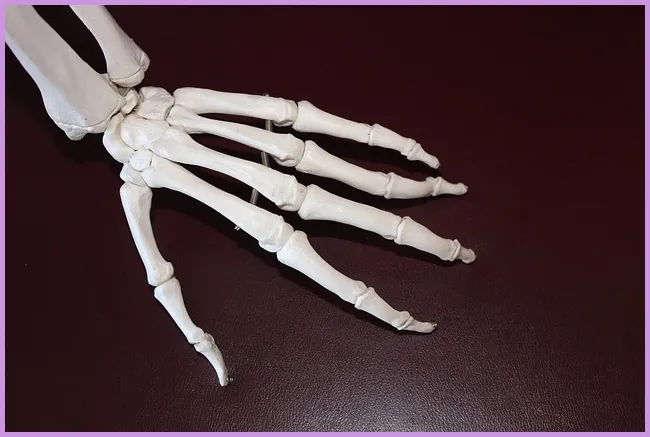

손가락 관절염의 이해

손가락 관절염은 일반적으로 두 가지 종류로 나뉩니다: 퇴행성 관절염과 류마티스 관절염입니다. 퇴행성 관절염은 나이가 들면서 발생하는 자연스러운 변화로 인해 관절의 연골이 마모되면서 통증과 염증을 초래합니다. 반면, 류마티스 관절염은 면역 체계의 이상으로 발생하는 자가면역 질환입니다. 이 두 가지 유형의 관절염은 치료법과 관리 방법이 다르기 때문에 정확한 진단이 중요합니다.